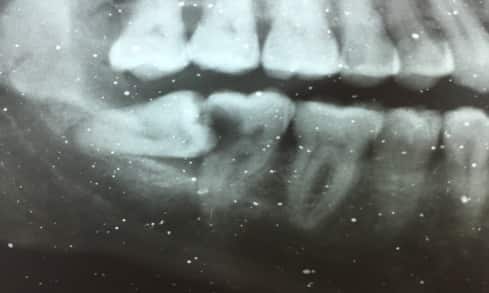

Otro caso que nos hemos encontrado en Centros Odontológicos Romano y que nos ha ayudado a responder a la pregunta de cuándo se deben extraer los dientes es el de un paciente hombre de 63 años, con movilidad dental generalizada y un dolor agudo en la zona inferior derecha. Una vez realizada la exploración en profundidad del caso, valoramos en su totalidad la situación de los dientes, especialmente de los que nos indica el paciente.

radiografia del primer molar extraidoEl primer molar inferior derecho y el segundo premolar inferior derecho presentan una pérdida de hueso muy evidente, teniendo como resultado la movilidad en los tres ejes del espacio, además de unos procesos de caries en estado avanzado con un fuerte compromiso de los nervios.

radiografia implante dentalValorando la situación clínica de ambas piezas dentales en cuando a su muy pronunciada movilidad y el estadío de sus caries, que provoca fuertes dolores, proponemos como mejor solución la retirada del molar y del premolar.